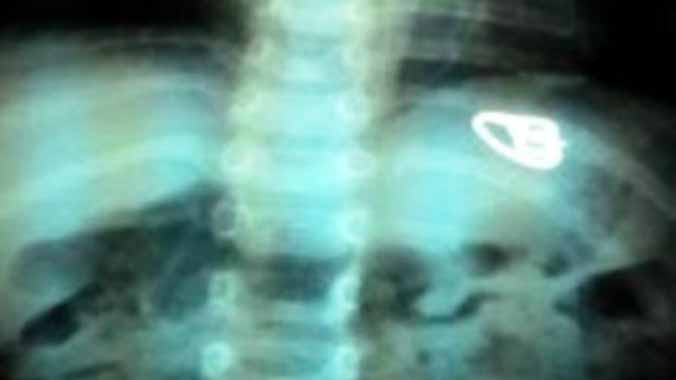

Phim X-quang cho thấy chiếc nhẫn nằm trong đường tiêu hóa bệnh nhi.

Bệnh nhi 2 tuổi nhập viện trong tình trạng đau bụng, đi tiêu ra máu, bụng cứng... Bé đã được điều trị ở bệnh viện địa phương 3 ngày nhưng không khỏi. Kết quả X-quang phát hiện dị vật trong đường tiêu hóa là một chiếc nhẫn có hạt. Bé được uống thuốc nhuận trường với dự kiến sẽ nội soi gắp dị vật.

Khi kiểm tra lại bằng X-quang, chiếc nhẫn đã xuống đến ruột già, bệnh nhân được tiếp tục cho uống thuốc nhuận trường. May mắn cuối cùng bé đã đi tiêu ra chiếc nhẫn hạt xoàn và không còn than đau bụng, không tiêu ra máu nữa, bụng mềm.